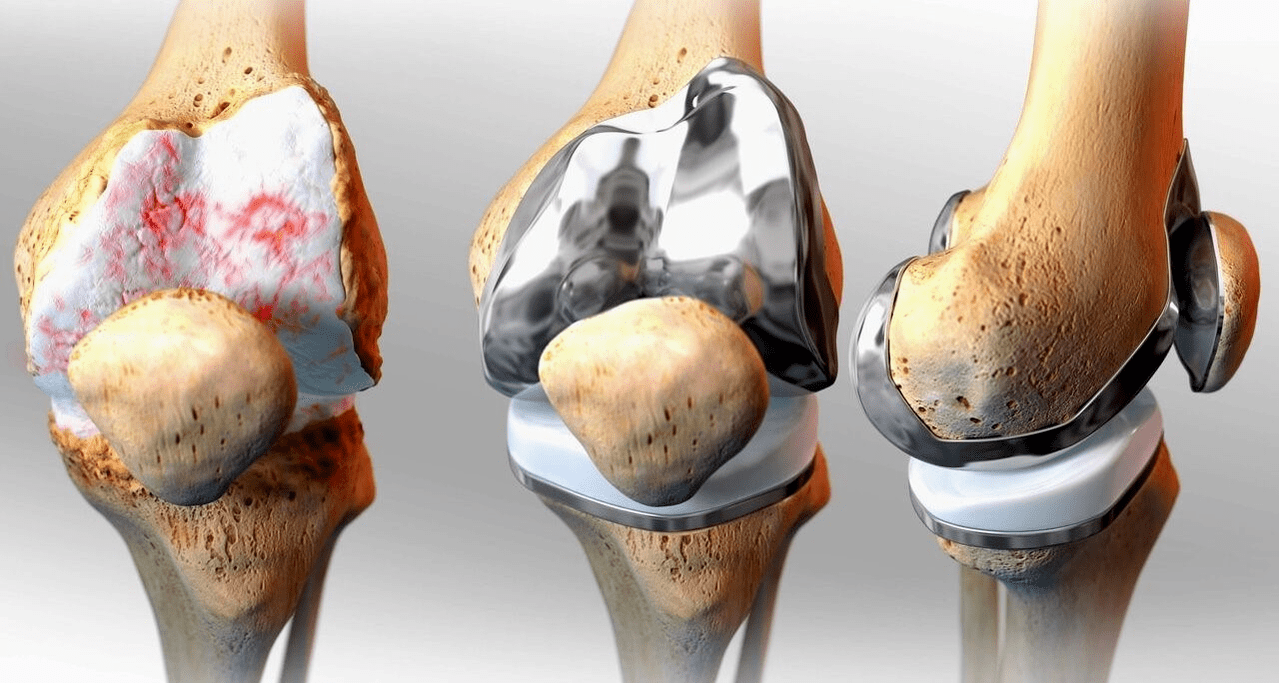

Surgical treatment and endoprosthesis

Endoprosthesis replacement is a widespread and effective surgical method in the treatment of severe gonarthrosis, which enables the preservation of the mobility of the limbs and the subsequent full life.This is a high-tech operation that takes about an hour and a half.In the postoperative period, long-term rehabilitation and development of the joint is necessary.After 25-30 years, when the artificial joint wears out, it must be replaced again.